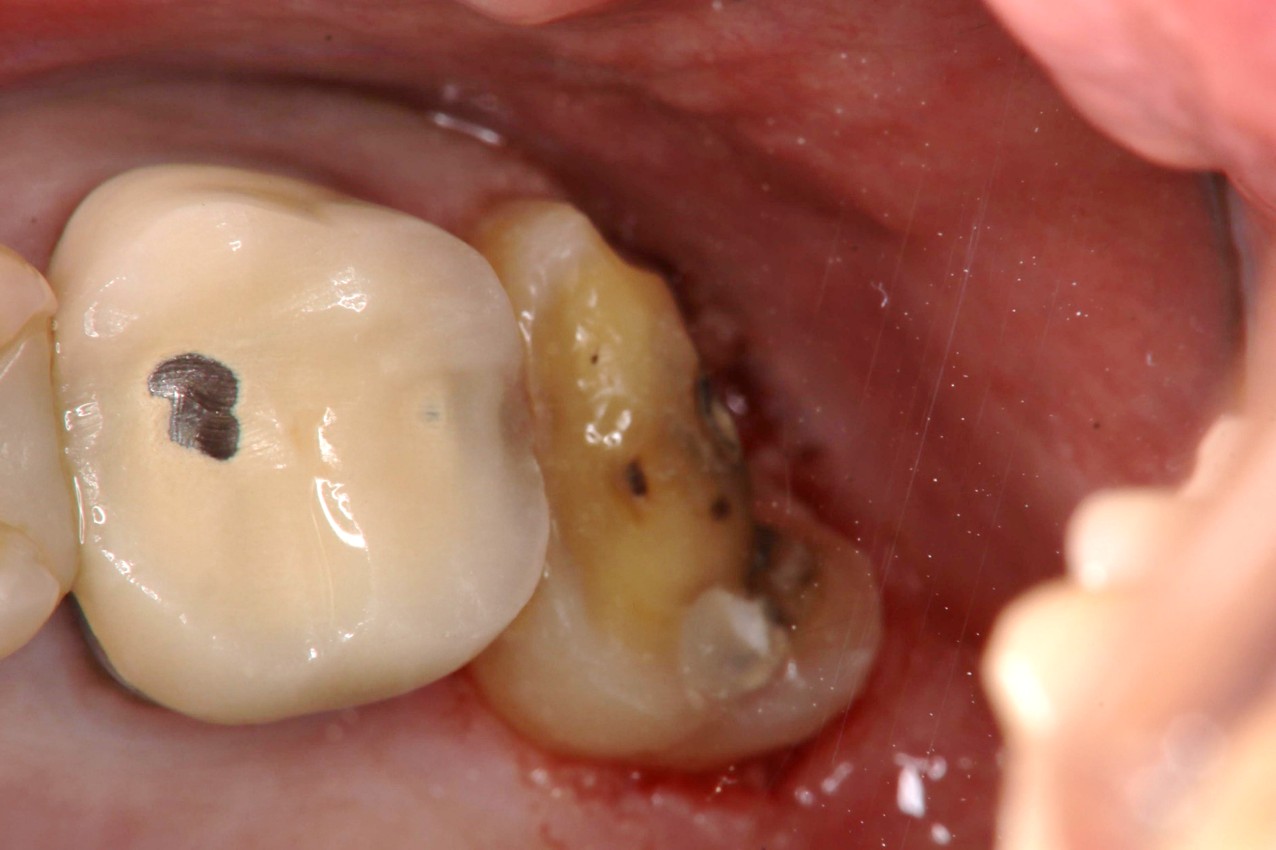

水雷射牙齦切除+冠塊體牙齒製備